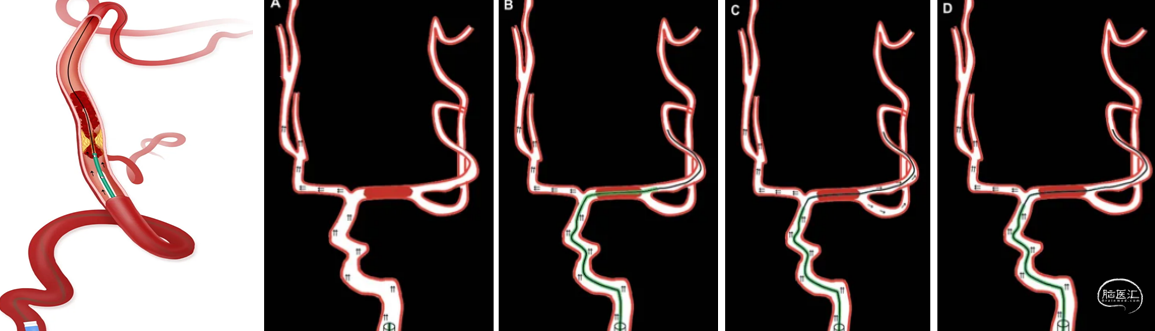

步骤3 将Fastunnel®跟进至远端,撤出微导丝,Fastunnel内造影确认位于血管真腔且无远端栓塞后,沿Fastunnel®沿Fastunnel®输送Syphonet®等取栓支架。下图1

步骤4 回撤Fastunnel®释放Syphonet®等取栓支架,6F中间导引导管/Tethys AS®等血栓抽吸导管造影观察局部管腔形态,若存在(束腰征)局限性狭窄则考虑是ICAS-AIS-LVO。下图2

步骤5 沿着支架推送杆,将Fastunnel®向前跟进使球囊覆盖狭窄病变部位。下图3

步骤6 球囊缓慢充盈扩张。下图4

步骤7 Fastunnel®球囊泄压,回撤Fastunnel®完全释放Syphonet®等取栓支架下图1

步骤8 利用Syphonet®等取栓支架远端锚定作用撤Fastunnel®球囊扩张微导管,前进Tethys®等中间导引导管/Tethys AS®等血栓抽吸导管。下图2

步骤9 SWIM抽拉结合取栓。下图3

步骤10造影确认狭窄程度,下图1。

步骤11 若残余狭窄程度≥70%,或存在局部限流性夹层,Fastunnel® 球囊扩张微导管沿微导丝重新到位,造影确认铆定狭窄部位。下图2

步骤12 撤出微导丝,沿Fastunnel球囊扩张微导管输送颅内自膨式支架(下图3)。

步骤13 调整张力,定位支架,沿Fastunnel®球囊扩张导管释放颅内支架。下图4